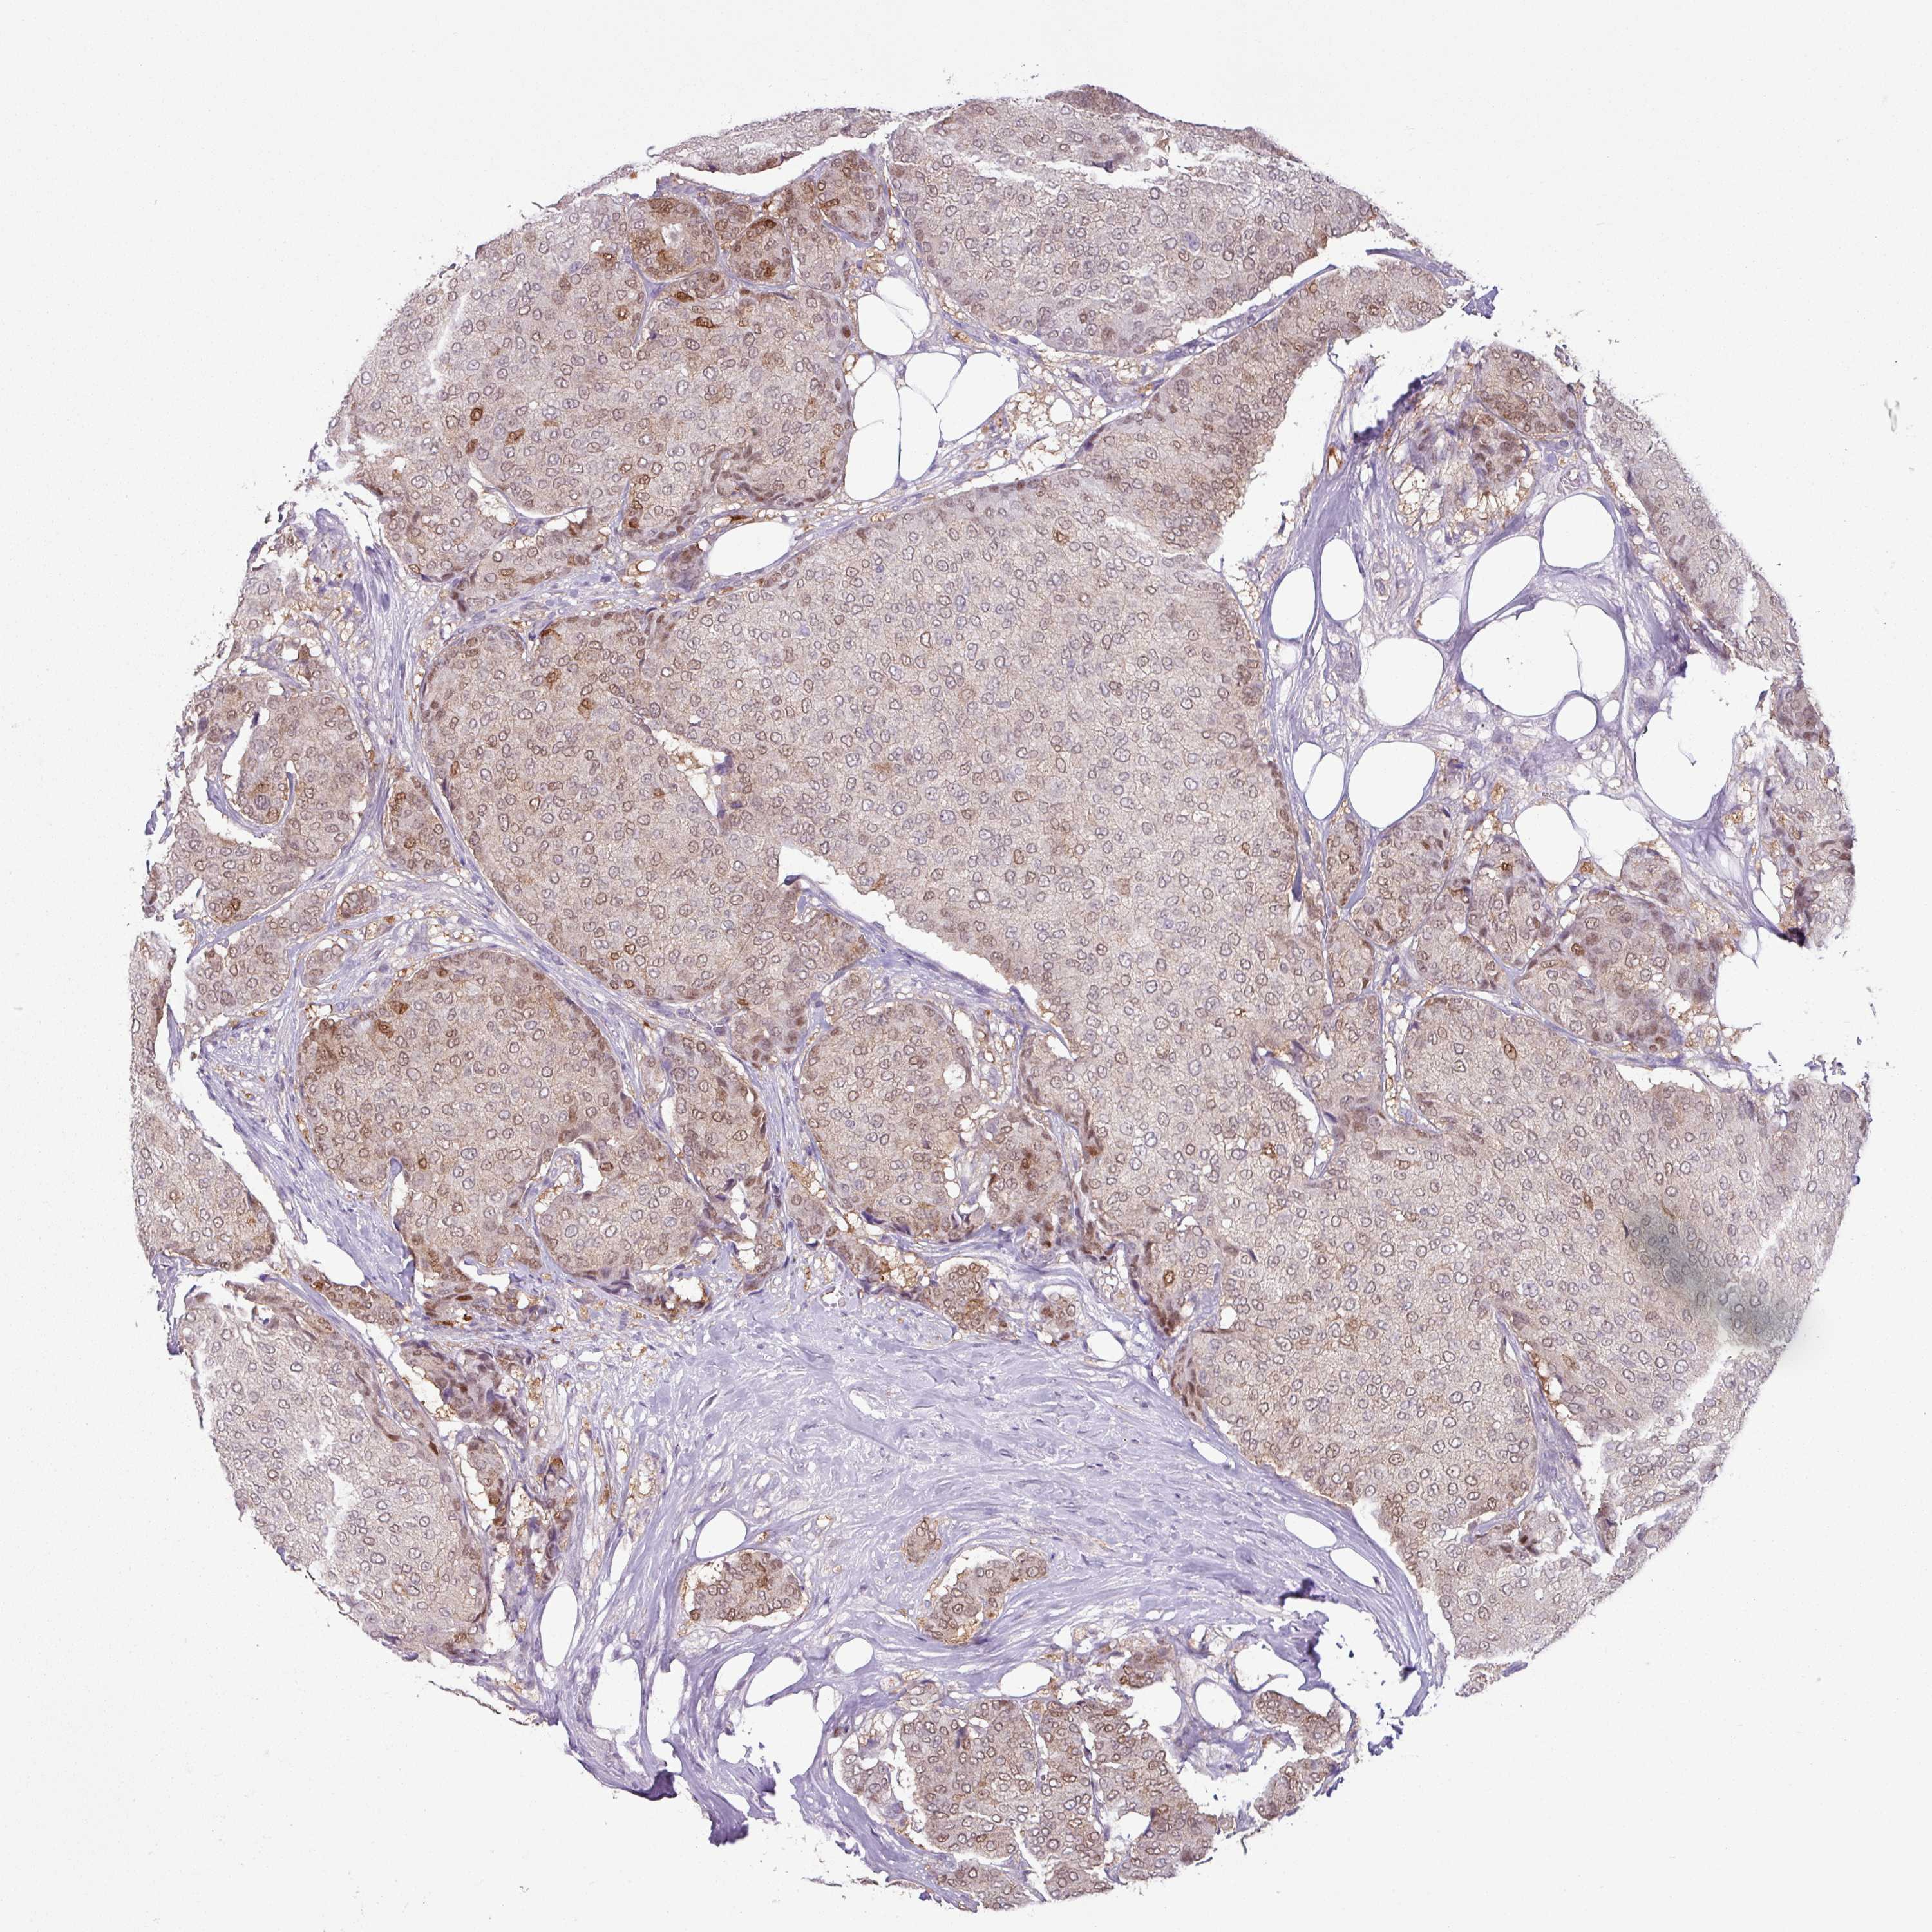

CANCER BREAST CANCER Show tissue menu

BRCA TCGA BRCA VALIDATION PROTEIN EXPRESSION